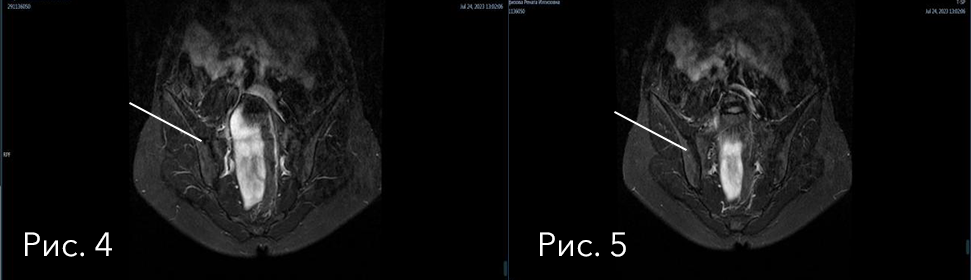

На данных изображениях (рис.1-2) можно увидеть «белое пятно» в проекции правого крестцово-подвздошного сочленения. Это ни что иное, как «активный» сакроилиит (отек костного мозга – воспалительные изменения кости), что для ревматолога подчеркивает видимую активность, подтверждая реальную неэффективность проводимой терапии.

В данном случае (рис. 3) на снимках "классический" вариант течения спондилита (будь то анкилозирующий спондилит или псориатический). В клинической практике не редки случаи отсутствия изменений в крестцово-подвздошных сочленениях, но выявляются отчетливые признаки спондилита - отека костного мозга в любом из отделов позвоночника, и это невозможно трактовать в рамках дегенеративных заболеваний позвоночника.